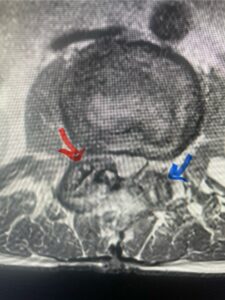

In this next case, this patient is a 47 year-old female who presents with intractable low back pain with severe pain, numbness, and weakness in the right lower extremity that had gotten progressively worse over a year. The patient had failed conservative management including physical therapy and epidurals. She was noted to have ⅘ weakness of plantar flexion. MRI demonstrated a large right L5-S1 disc herniation with severe compression of the descending right S1 nerve root (Fig 3). It was decided to perform a right L5-S1 hemilaminectomy for removal of the disc fragment and decompress the S1 nerve root. When you expose the disc, one must be certain to release any anterior adhesions to the nerve root in order to prevent a dural tear during retraction of the nerve root. It is also important to make sure during exposure and you finally encounter the dura after removing the ligamentum and fat, to make sure you are looking at the nerve root and not the main trunk of the thecal sac because if you don’t you can avulse or damage the nerve root if you retract the wrong structure.

Fig. 3a: Sagittal and axial T2-weighted lumbar MRI images demonstrating large right L5-S1 disc herniation (red arrows)

Fig. 3b

We found a massive subligamentous herniation which had to be revealed by having your partner retract the freed nerve root with a nerve root retractor and putting slight downward pressure on the more medial and anterior disc space. There is nothing more satisfying when the jelly (disc fragment) of the annulus (donut) comes squirting out and you remove a large chunk of disc material that clearly was stretching the ligament membrane and compressing the nerve root. This does cause back pain in addition to radiculopathy not only by the component of mechanical compression but also the stretching of the nerves within the ligament. We performed this surgery and noted that the nerve root was a very angry red color or hyperemic and we removed a large subligamentous fragment. The patient had improvement of her preoperative radicular symptoms.